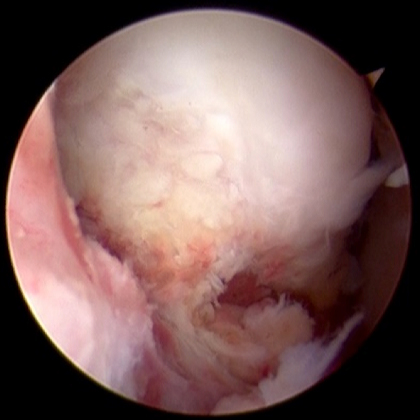

肩関節鏡手術

肩が外れやすい場合(反復性肩関節脱臼)は、基本的に関節鏡下バンカート修復手術で対応していますが、ラグビーなどのコンタクトスポーツ、再発リスクの高い症例に対しては烏口突起移行術を含めて、関節鏡下バンカートブリストウ法で対応しています。

五十肩や肩腱板断裂を含む肩の痛みに対しては、まずは肩関節治療に対する経験豊富なスタッフによるリハビリを行った上で、必要に応じて関節鏡下授動術や関節鏡下腱板修復術を行っています。

鏡視下腱板修復術